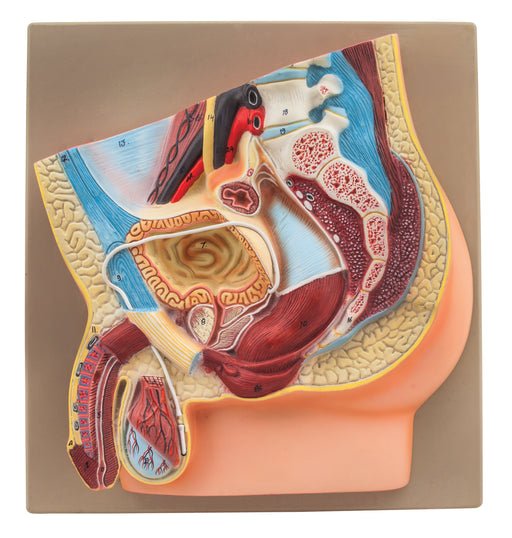

Female Muscle Pelvis - 4 Parts

Female Pevis Model separates into 4 parts because of median section and the removable inner organs.Representation of the external and internal geni...